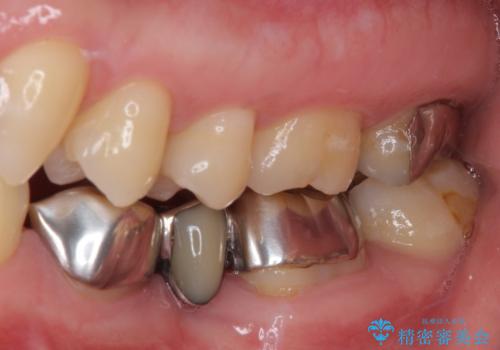

抜歯してからインプラント埋入までには時間がかかるため、その間に下顎左右臼歯の金属のブリッジをオールセラミックへ変えていくこととしました。

継ぎ接ぎだらけの上顎前歯もオールセラミッククラウンにて審美的に改善したいとのことでしたが、捻れが強くあるため、事前に矯正治療で歯列を整えてから、補綴治療を行うこととしました。

目立つ部分の銀歯や気になる変色歯をまとめてきれいに仕上げることができました。